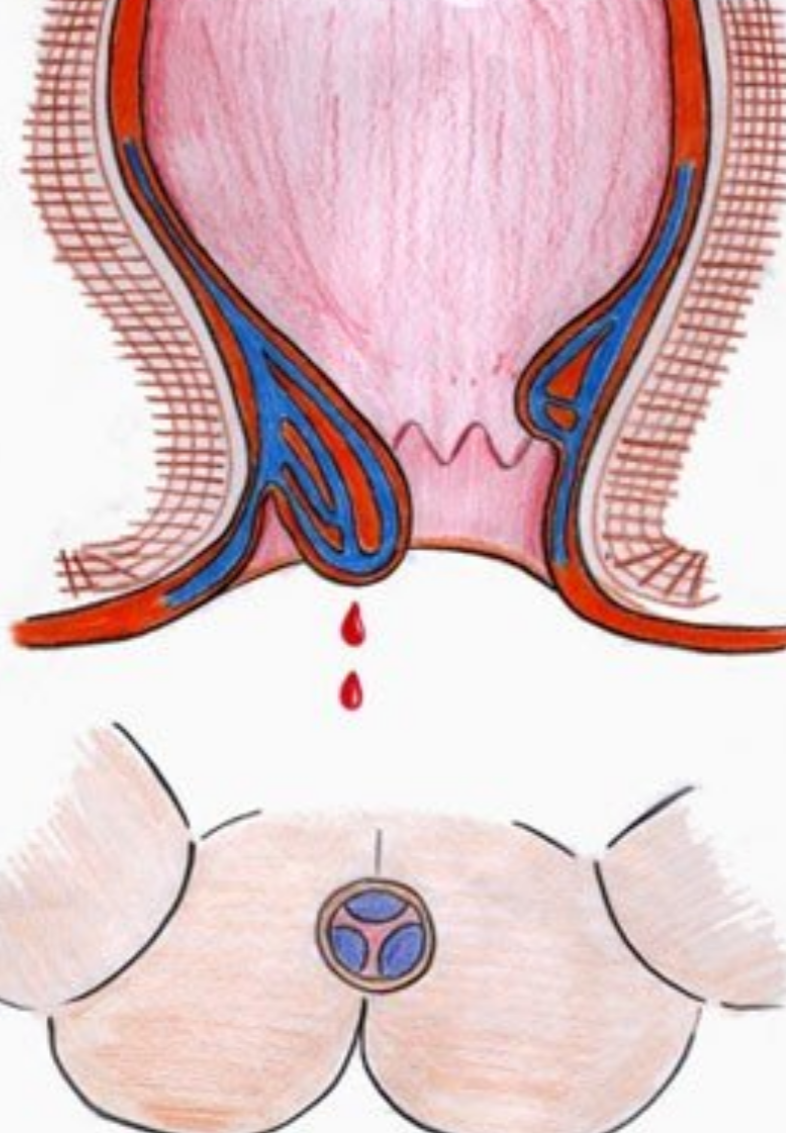

人工陰道漫畫的

治療中人工陰道漫畫

人工陰道漫畫

治療中人工陰道

治療中人工陰道漫畫

治療中人工陰道的

正在治療的人工陰道

治療中的人工陰道的

治療中的人工陰道

正常人工陰道的

正常人工陰道

幼兒人工陰道

正常的人工陰道的

正常的人工陰道

正常女性人工陰道

人工陰道治療中的

人工陰道作用

人工陰道治療

人工陰道治療前期

人工陰道治療前後